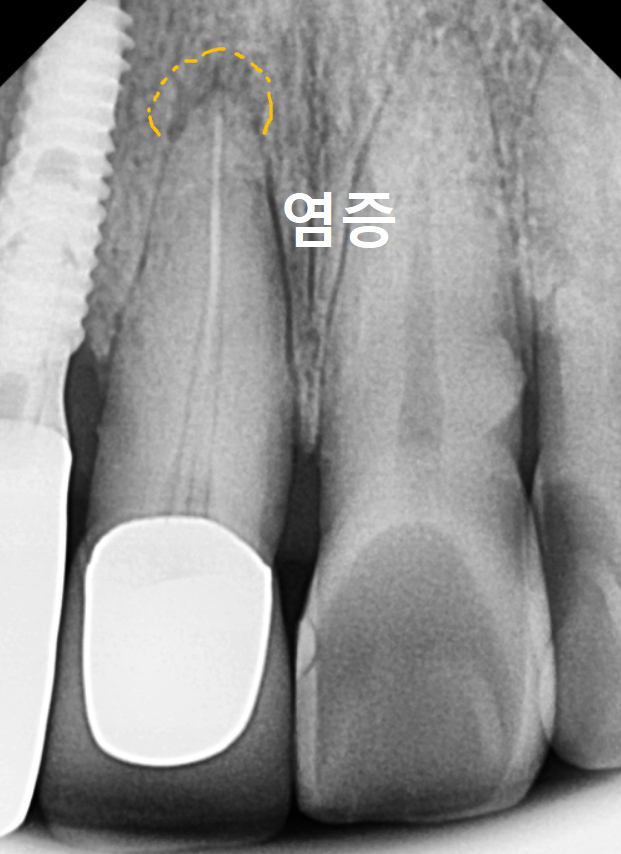

CT 분석 결과 중앙 앞니(#11) 치아 뿌리 끝에

염증이 발견되었지만,

환자분께서 최대한 자기 치아를

더 써보고 싶어 하셔서

일단 흔들림이 심한 오른쪽 앞니(#12)만

발치하고 임플란트를 진행했습니다.

C뿌리 끝 염증도 더 심해진 상황...

251125

안타깝지만 이 치아도 발치 후

임플란트로 재건하기로 결정했습니다.